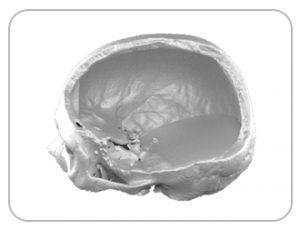

DEFECT DUE TO STROKE

DESIGNED IMPLANT

IMPLANT FABRICATED WITH POROUS TITANIUM